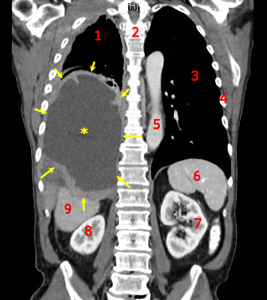

- 증상(종양, 출혈, 통증 등), 영상검사(CT, MRI 등), 조직검사 등으로 진단합니다.